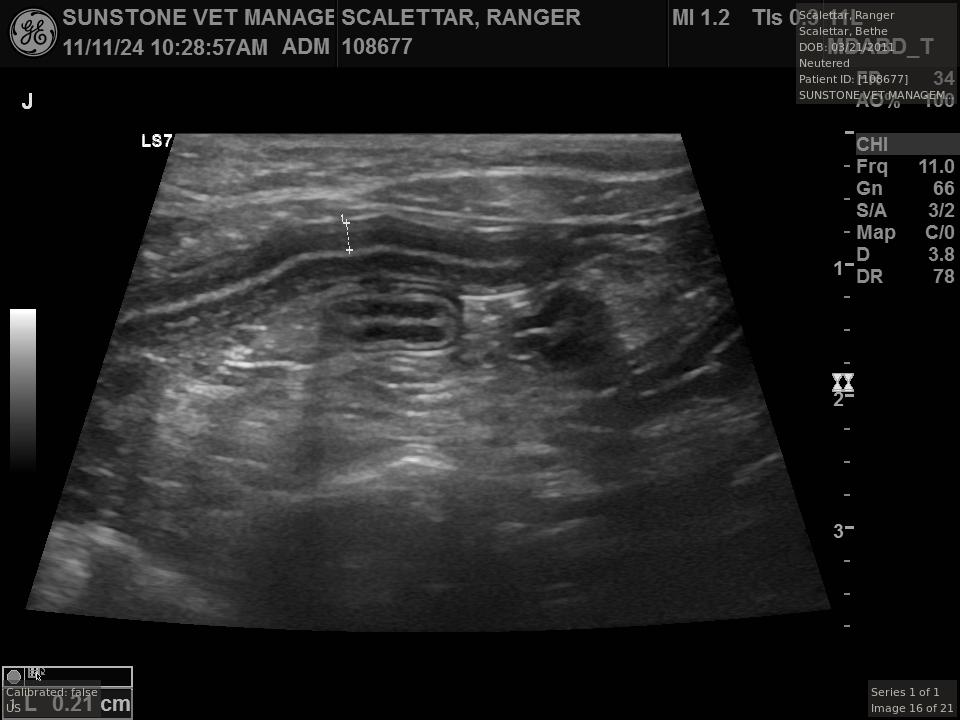

The veterinarian generated a series of images showing different organs and substructures by

changing the position and orientation of the ultrasound transducer. The images were collected

in a defined order, which is repeated from patient to patient, ensuring that nothing is missed. In

Ranger's case, the sonographer collected about twenty images during an examination that

lasted about fifteen minutes.

The sonographer stated that Ranger's ultrasound images were largely normal for an older cat. In particular, they show changes in the kidneys that are commonly noted in geriatric cats and that reflect a risk for the development of chronic kidney disease. However, the images did not show any significant abnormalities in Ranger's stomach, intestines, and associated lymph nodes. Nonetheless, the results did not rule out recurrence of Ranger's small cell lymphoma.